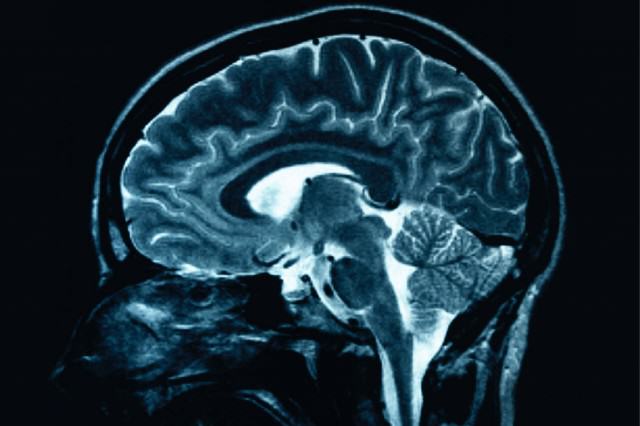

One explanation, that B.T. was “malingering,” or lying about her disability, was disproved by an EEG test. When B.T. was in her two blind states, her brain showed none of the electrical responses to visual stimuli that sighted people would display – even though B.T.’s eyes were open and she was looking right at them.

Responsibility for the information “gatekeeping” that kept B.T. from seeing everything she looked at may lie with the lateral geniculate nucleus, a sort of neural relay center that sends visual information down synaptic pathways into the brain’s information processors.